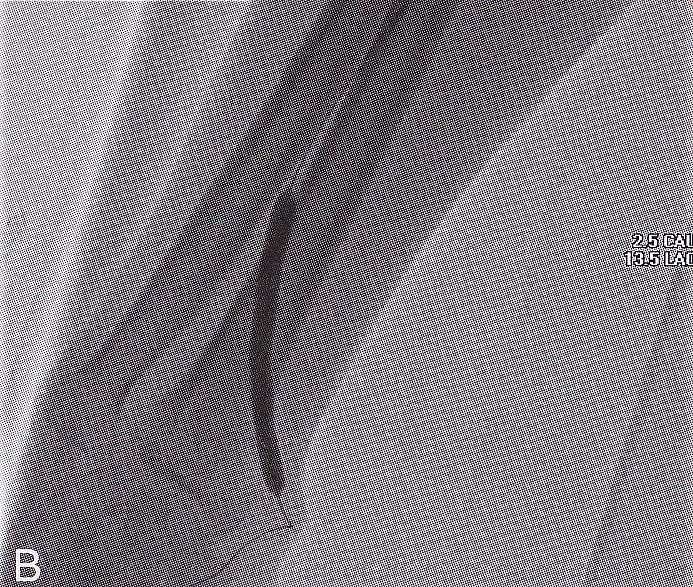

Circuit VesperⅡは、シャントPTAを中心とした教育・トレーニングおよびカテーテル評価を目的としたシミュレーターです。

あえて腕などの周辺構造を排除し、シャントPTAに集中できる設計とすることで、血管全体を立体的に、かつ目視で把握できる環境を整えました。

コンパクトな設計で全体像を見渡しやすく、必要な触感や構造を的確に再現することで、よりリアルな手技感覚と臨場感を構築します。